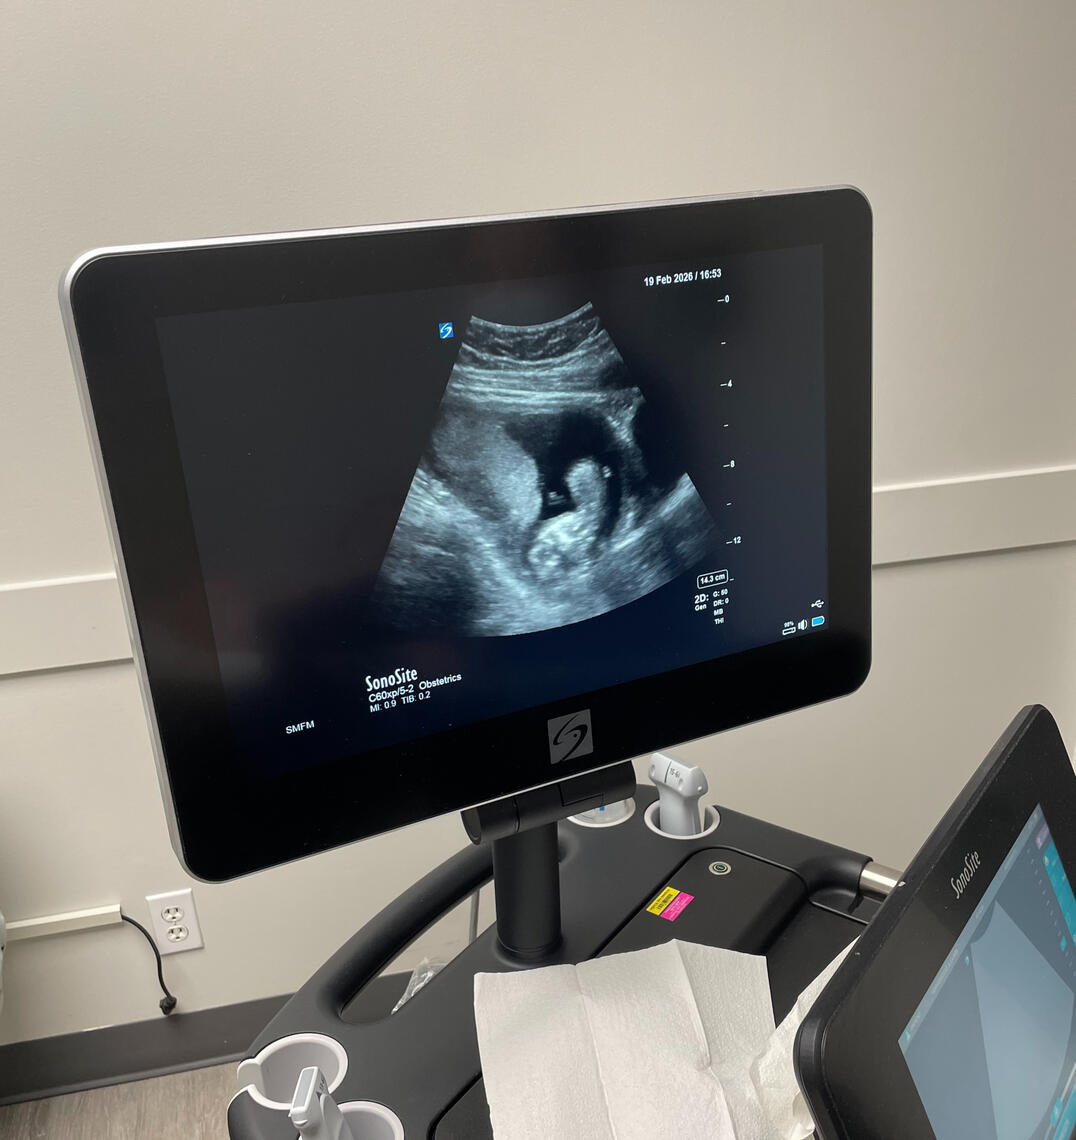

Ultra sound @ March 25th

It has only been three months and three weeks since we found out we are having a child.Since then, we have gained a bassinet in our bedroom and a closet filled with new baby clothing. New artwork for our nursery and overall has been the subject of conversation every single day since.It is sufficient to say that our lives have changed forever.Having this drastic a change in such a short time has come with much stress and complications, and almost all aspects of our lives.Most surprising are the emotional changes we have undergone over the past three months. As it turns out, (from parenting books and colleagues’) husbands and wives will go through drastic hormonal changes while the wife is pregnant.All this has led to a lot of planning for our future baby. There are times when I feel more stress than I've ever felt in my entire life.However, in the same breath, I believe I have also felt the most gratitude and love for my family that I have ever felt.For sure, things are differentBut overall, despite all the sleepless nights and worrying about our baby’s future, I’ve been able to see the world in a different, more positive light than ever before.Abree and I have been dreaming of this moment and have been planning for our new child. Now that it is here, it feels almost surrealWe are very excited